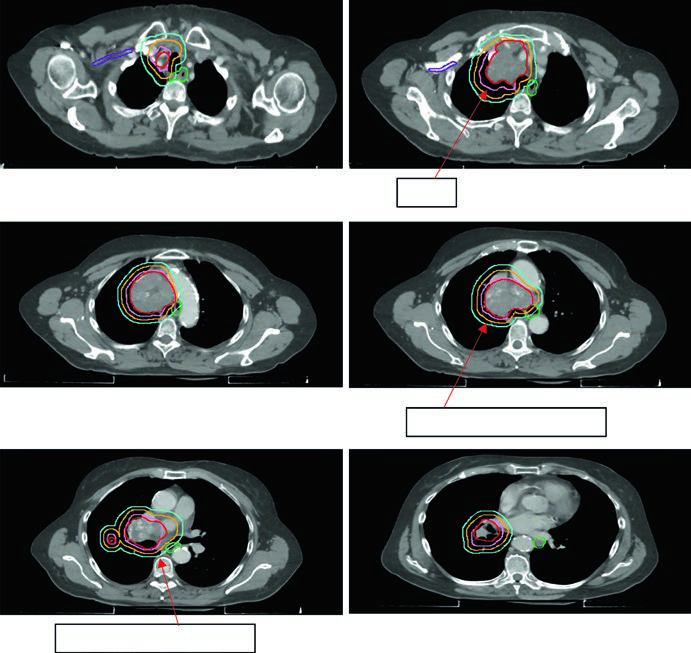

CPPC: irradiação de campo envolvido em doença limitada e extensiva

O carcinoma de pequenas células apresenta radiorresistência relativa e crescimento rápido, mas é sensível à irradiação combinada à quimioterapia. A abordagem de campo envolvido é aceita em ambos os estádios.

A expansão GTV → CTV no CPPC é de 0,5 a 1,0 cm, frequentemente incluindo o hilo ipsilateral mesmo sem captação PET demonstrada, dado o padrão de drenagem linfática. As margens CTV → PTV seguem as mesmas diretrizes do CPNPC, calibradas pelo sistema de IGRT disponível.

Os esquemas de dose diferem por estádio:

- Estádio limitado: 45 Gy em 1,5 Gy duas vezes ao dia (30 frações) — o esquema clássico de Turrisi — ou 66–70 Gy em 2,0 Gy diário como alternativa de dose mais alta

- Estádio extensivo (consolidação): 30–45 Gy em 3,0 Gy/fx no sítio de doença volumosa

A Figura 13.6 mostra um caso cT2N2 de estádio limitado com o campo envolvido cobrindo tumor primário e linfonodos mediastinais comprometidos, mas excluindo cadeias eletivas. O esquema utilizado foi 45 Gy/30fx BID.